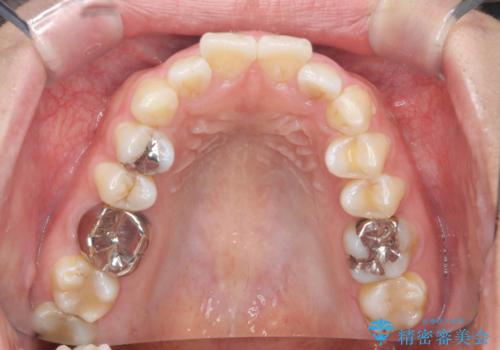

前歯の角度を改善するマウスピース矯正

- 前歯の角度・重なりの改善を求めて矯正治療を希望され来院されました。

通常このような場合、小臼歯を4本抜去しワイヤー矯正を行う治療計画も検討されますが、今回は側方に拡大できる骨量が十分に存在したため抜歯をしない矯正治療の計画を立てます。

しっかりと拡大を行い、IPRも併用したことで歯並びと前歯の角度を大幅に改善することができました。